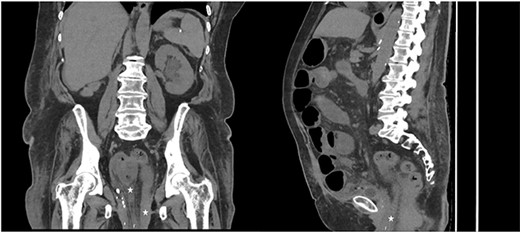

Computed tomography (CT) of the abdomen and pelvis demonstrated evidence of small bowel obstruction and perineal hernia a 5 cm defect containing a loop dilated small bowel with mesenteric congestion. There was collapsed small bowel exiting the hernia defect. Overall, the clinical and radiological findings were suggestive of incarcerated small bowel that had herniated through a perineal hernia and prolapsed through the vaginal vault (Fig. 2).

CT coronal (left) and sagittal (right) of abdomen and pelvis, demonstrating extension of small bowel into the pelvis (marked with star) consistent with perineal hernia.